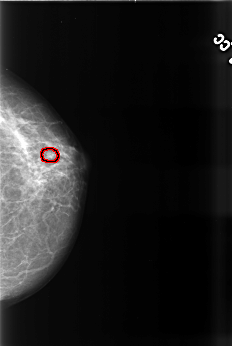

B_3471_1.LEFT_MLO

LEFT_MLO LINES 4544 PIXELS_PER_LINE 3064 BITS_PER_PIXEL 12 RESOLUTION 50 OVERLAY

FILE: B_3471_1.LEFT_MLO.OVERLAY

TOTAL_ABNORMALITIES 1

ABNORMALITY 1

LESION_TYPE CALCIFICATION TYPE PUNCTATE-PLEOMORPHIC DISTRIBUTION CLUSTERED

LESION_TYPE MASS SHAPE ROUND MARGINS MICROLOBULATED

ASSESSMENT 4

SUBTLETY 3

PATHOLOGY BENIGN

TOTAL_OUTLINES 1

BOUNDARY